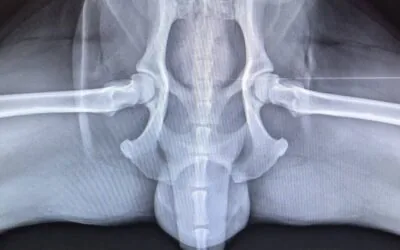

Szczenię dużej rasy

Idealny moment na badanie w kierunku dysplazji to wiek 3,5 miesiąca. Dysplazja długo nie daje objawów. Wczesne RTG to szansa na szybką reakcję i lepszą przyszłość Twojego psa.